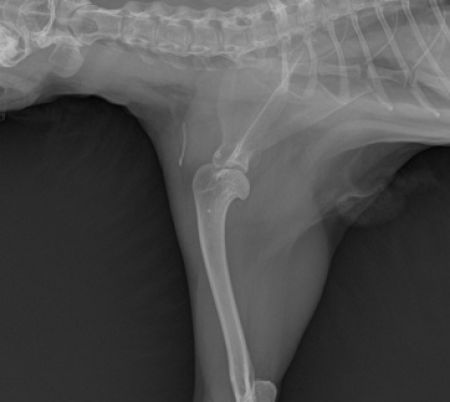

Sold

Humerus